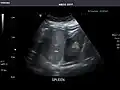

Liver

Ultrasonography of the liver with some standard measurements[6]

In patients with deranged liver function tests, ultrasound may show increased liver size (hepatomegaly), increased reflectiveness (which might, for example, indicate cholestasis), gallbladder or bile duct diseases, or a tumor in the liver.

Ultrasonography of liver tumors involves two stages: detection and characterization. Tumor detection is based on the performance of the method and should include morphometric information (three axes dimensions, volume) and topographic information (number, location specifying liver segment and lobe/lobes). The specification of these data is important for staging liver tumors and prognosis. Tumor characterization is a complex process based on a sum of criteria leading towards tumor nature definition. Often, other diagnostic procedures, especially interventional ones, are no longer necessary. Tumor characterization using the ultrasound method will be based on the following elements: consistency (solid, liquid, mixed), echogenicity, structure appearance (homogeneous or heterogeneous), delineation from adjacent liver parenchyma (capsular, imprecise), elasticity, posterior acoustic enhancement effect, the relation with neighboring organs or structures (displacement, invasion), vasculature (presence and characteristics on Doppler ultrasonography and contrast-enhanced ultrasound (CEUS).

Liver: Diffusely homogeneous and normal in echogenicity. No focal mass or contour nodularity. No intrahepatic biliary ductal dilatation.